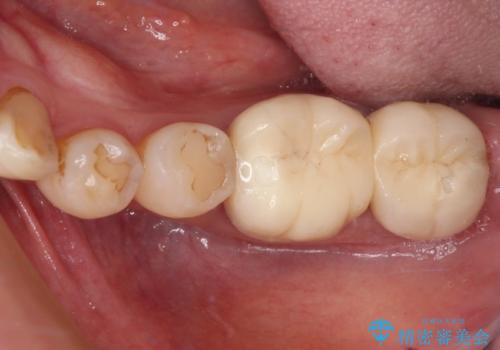

セラッミクインレー|オールセラミッククラウン|銀歯による二次カリエス|ラバーダムシート使用

担当医 河野豊嘉